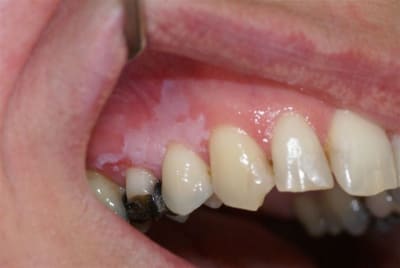

pas de douleur, pas de saignements, bords irréguliers, depuis plusieurs mois, 1ére consultation, légèrement ulcéreux en regard de la 15.

pas du tout c est une tres classique leucoplasie homogene . Ca demande un certain suivit. Effectivement si tu n ' as pas l habitude adresse.

C'est surtout l'ulcération qui interroge: soit elle est d'origine traumatique et doit cicatriser sans traitement sous 15 jours -> dans ce cas surveillance semestrielle du lichen, soit elle ne cicatrise pas et alors c'est biopsie sans attendre.

Surtout ne rien prescrire: il faut voir si la lésion cicatrise seule ou non.

Apparemment la 15 portait une couronne: un galvanisme peut-être à l'origine du lichen.

De plus la perte de la couronne entraîne la perte du bombé vestibulaire et de sa déflexion alimentaire qui pourrait expliquer la blessure traumatique de la gencive.

Hypothèse à vérifier.

Et le gagnant est Tillc :

résultat de l'examen histo : leucoplasie marquée, homogène, inflammation chronique du chorion.

N'ayant pas l'habitude du suivi de ce genre de lésion, j'adresse au stomato.